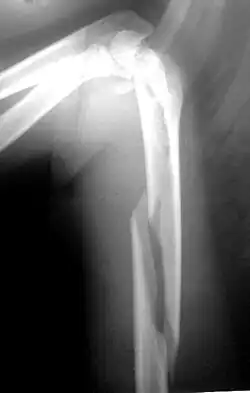

Fratura de úmero se refere a ruptura do úmero, o maior osso do braço. As fraturas proximais são próximas ao ombro (25% dos casos), mediais na diáfise (60% dos casos) e as distais ocorrem próximo ao cotovelo (15% dos casos). Essa classificação pode ser subdividida, com base na extensão da fratura e nas partes específicas do úmero. [1]

Quando há suspeita clínica são solicitadas duas radiografias, frente e perfil ou duas oblíquas, dependendo do local afetado. Tomografia computadorizada pode dar mais informações sobre a fratura.[8]